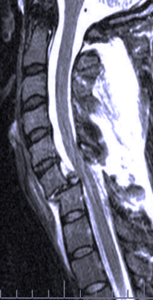

Spinal Trauma and Fractures

Spinal injuries can be serious life threatening problems that cause paralysis requiring complex surgical repair and others are lesser injuries that my only result in transient pain that are treated with a brace or collar while they heal. Fractures can occur in various regions of the spine and must be evaluated by a spine surgeon with experience in these injuries.